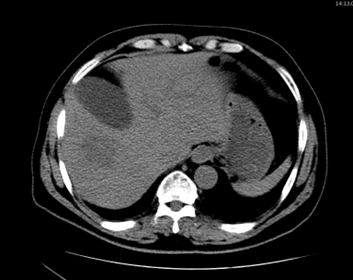

환자의 임상 증세를 고려하였을 때 화농성 간농양(pyogenic liver abscess)으로 판단되었으며, 경피적 배액술과 경험적 항생제 (3세대 세팔로스포린계열) 치료를 시작하였다. 이후 임상 경과는 점진적으로 호전되었으나, 추적검사로 상태 안정된 후 조영제를 사용한 역동정 조영증강 CT 검사에서 총담관 확장 소견이 동반되어 [그림3] 추가적인 원인 평가를 시행하였다.

[그림 3] 원위부 담도의 확장 소견

측시(side-view) 내시경 검사에서 Vater 팽대부 부위 종괴가 확인되었고 [그림4], 조직 검사 결과 선암종(adenocarcinoma)으로 확진되어 Vater 팽대부암으로 최종 진단되었다. 본 증례는 간농양을 초기 임상 증상으로 하여 기저 악성종양이 진단된 경우로, 감염성 질환의 원인 평가에서 위장관 악성종양의 중요성을 시사하는 임상적으로 의미 있는 사례이다.